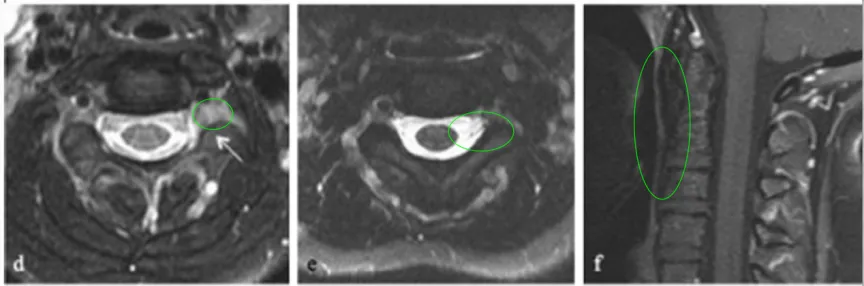

此时,治疗来到了第二步——个体化放疗。结果显示小凡对70gy光子放疗反应良好,幸运的是,孩子的耐受性也很好,治疗十分顺利,放疗后的残留病变明显变小,也无明显放疗副作用。

时间过去了10年,一个令所有人意想不到的奇迹已然发生:小凡的脊索瘤仍未复发,也没有出现神经功能缺陷,这个曾被认为5年不复发率仅为20%左右的脊索瘤,竟然就这样成为“破例”!